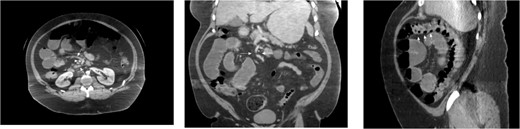

A 45-year-old morbidly obese male with a history significant for morbid obesity and atrial fibrillation presented with 1 day of abdominal distension, oral intake intolerance, nausea, and vomiting. The patient had no history of abdominal surgery. Physical exam revealed a soft, distended abdomen without peritoneal signs. Laboratory evaluation revealed normal blood cell counts and electrolytes. A CT-scan of the abdomen and pelvis with IV and PO contrast was performed which demonstrated proximal small bowel dilation and a significant amount of small bowel posterior to the SMA. A mesenteric swirl was also observed on CT imaging. The CT scan images are presented below (Fig. 4). Based on the concern for closed-loop obstruction and probable paraduodenal hernia, the patient was taken for diagnostic laparoscopy. During the procedure the patient was noted to have marked small bowel dilation, and most of the small bowel was found incarcerated behind the ascending mesocolon. The laparoscopic approach in this patient was significantly hindered by the excessive intraperitoneal fat present from his morbidly obese state. The procedure was converted to an upper midline laparotomy which facilitated complete reduction of the hernia and evaluation of the incarcerated bowel. Post-reduction, the bowel was deemed well perfused and viable. The internal hernia defect was confirmed as Waldeyer’s fossa based upon its position between the SMA and the ligament of Treitz. The hernia sac was opened laterally by mobilizing the cecum and ascending colon, taking down the white line of Toldt and medializing the ascending colon and cecum. Appendectomy was performed. The operation was completed without complication and the patient recovered well.

CT images for Case 2, axial, coronal, and sagittal, respectively. Note the mesenteric swirl (arrows in axial and coronal images) around the SMA (single arrowhead in axial and coronal images). This represents the posterior torsion of the small bowel mesentery as it courses into Waldeyer’s fossa toward the right retroperitoneum. The resulting dilated small bowel can be seen in the right upper quadrant. Also note the anterior course of the proximal transverse colon (three arrowheads in the sagittal cross-section) as it has been pushed toward the anterior abdomen due to the significant mass of dilated small bowel which is now posterior to its mesentery.